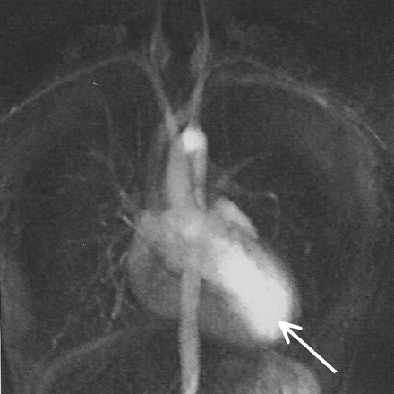

| Fig. A (above), 23-year-old woman referred to MRI with suspicion of transposition of great arteries because of prominent trabeculation of subaortic ventricle in echocardiography. Time-resolved coronal maximum-intensity-projection angiograms (B-C, below) and cine short-axis view (D, bottom). The angiograms show normal time course of enhancement of subpulmonary atrium and ventricle and pulmonary arteries (A); and enhancement of pulmonary veins, subaortic atrium, ventricle, and aorta (B). Note decreasing enhancement of subpulmonary ventricle from A to C, indicating absence of relevant left-to-right shunt flow. This patient suffered from noncompaction myocardium, which is visualized on time-resolved MR angiography (C) (arrow) and is shown on cine short-axis view (D) (arrows). Republished with permission of the American Roentgen Ray Society from AJR 2006; 187:1107-1114. |